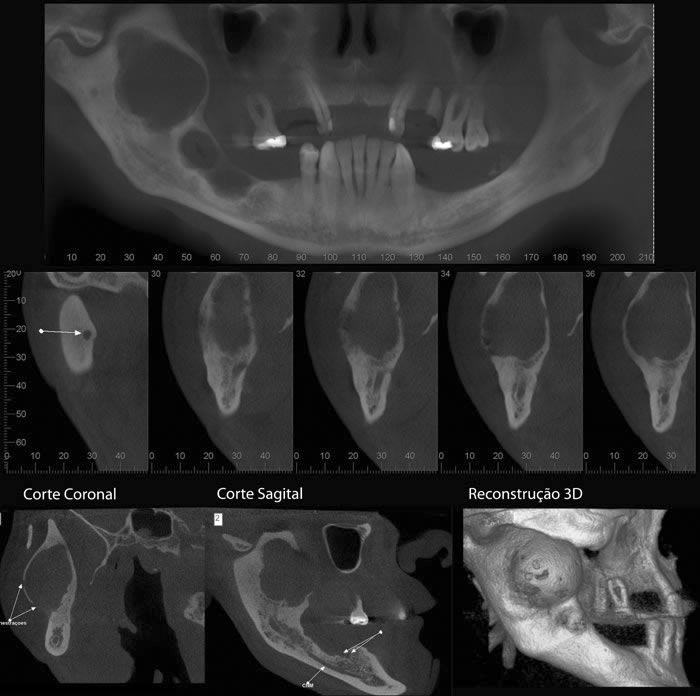

Caso 5: Dente retido

Dente 47 e 48 retidos, em posição mésio horizontal, sobrepostos com raízes superpostas ao canal mandibular. Ao exame tomográfico identifica-se o canal passando rechaçado entre os ápices do 48 e a cortical vestibular e passando entre as duas raízes mesiais do dente 47.

Caso 6: Reabsorção

Achado radiográfico, na radiografia periapical de rotina, nota-se área de menor densidade na distal cervical e alteração no contorno na mesial, e rarefação óssea periapical. Ao exame tomográfico pode-se observar o dente 11 com osteólise apical e área de reabsorção na distal e reabsorção por substituição na mesial.